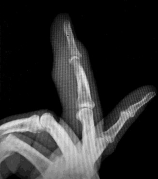

Question 2:

A 6-year-old boy falls on an outstretched hand. Radiographs of the elbow are shown below: On physical examination, the child is unable to flex the interphalangeal joint of the thumb. Which nerve is most likely injured?

Correct Answer: Anterior interosseous nerve

Explanation:

The inability to flex the interphalangeal joint of the thumb indicates an injury to the flexor pollicis longus (FPL), which is innervated by the Anterior Interosseous Nerve (AIN). AIN neuropraxia is the most common nerve injury associated with extension-type supracondylar humerus fractures.